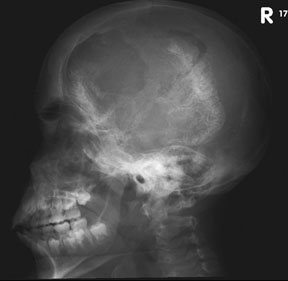

STURGE-WEBER SYNDROME Sturge (1879) reported the case of a child with facial “port-wine stain,” epilepsy, buphthalmos, and a dark choroid.204 Schirmer had noted the association of the facial vascular malformation and glaucoma in 1860.3 Weber (1922) reported brain X-ray findings of parallel streaks (“railtrack” sign), which he interpreted to represent calcific changes (Fig. 19).205